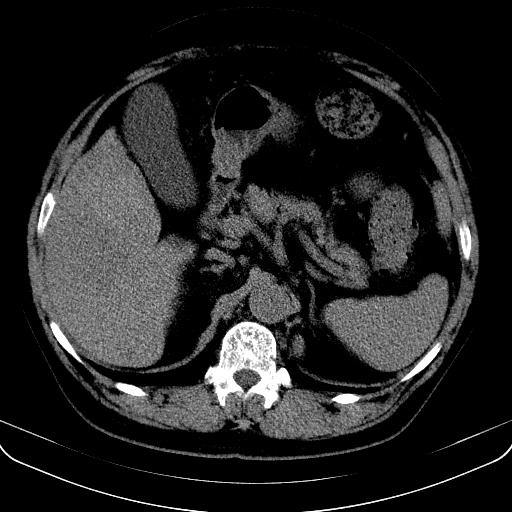

以下是引用jia119在2008-3-5 13:31:00的发言:[br]肝内多发片状低密度影,密度不均,我还是考虑肝ca可能,另肝内小囊肿,胆囊增大。

以下是引用形影不离在2008-3-5 12:18:00的发言:[br]肝硬化伴门脉高压征,肝内占位待排,增强再说.

以下是引用随光逐影在2008-3-5 21:11:00的发言:[br]肝硬化伴门脉高压(食管下段静脉曲张),肝癌不排除。建议:行ct增强扫描检查。

以下是引用同在2008-3-5 13:56:00的发言:[br]考虑肝癌可能性大,胆囊增大.